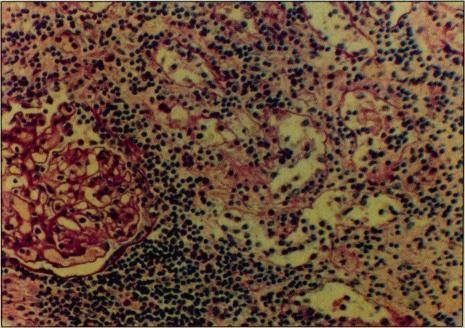

Spontaneous renal allograft rupture, an unusual complication of renal transplantation, occurred in a 35-year-old woman 10 days after transplantation. Unusual localized pain and tenderness at allograft site, oliguria, and hypotension, a triad frequently seen in renal allograft rupture, were present. Management by transplant nephrectomy was inevitable because of the patient's downhill course. Histopathologic findings diagnostic of acute allograft rejection support current thinking that spontaneous rupture may be the final outcome, although unusual, of renal allograft rejection.